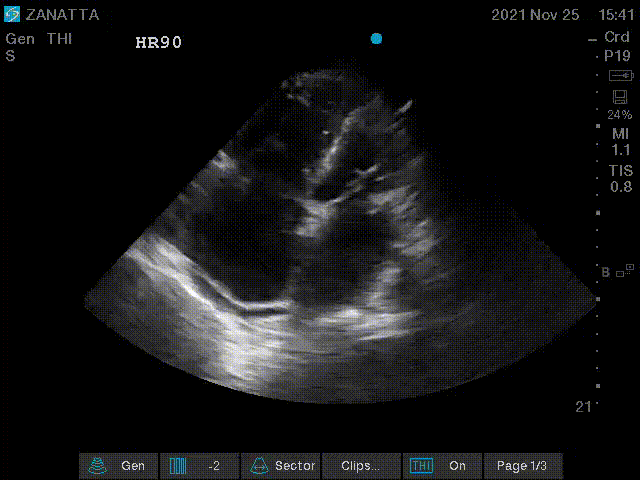

You move on to the parasternal long and short axis views.

Parasternal Short Axis